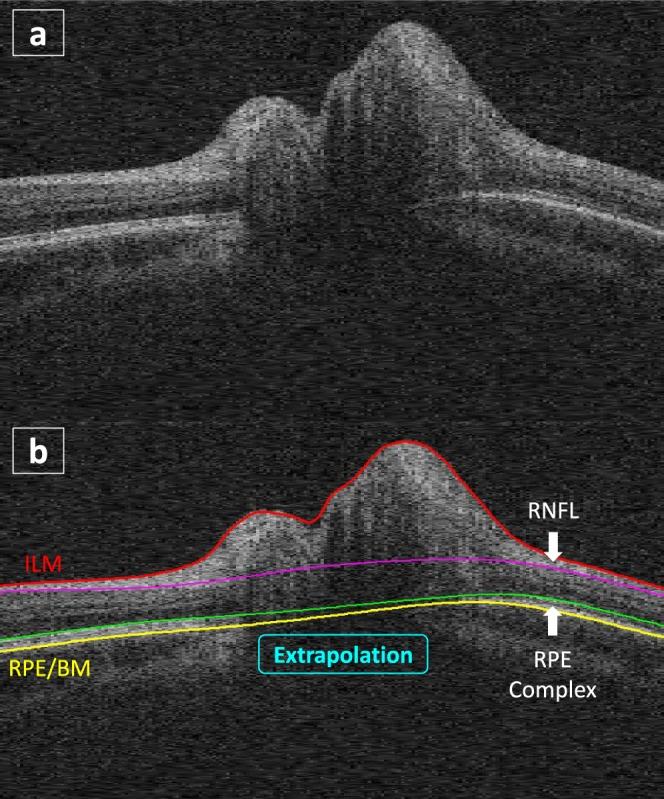

Recent studies indicate that the amount of deformation of the peripapillary retinal pigment epithelium and Bruch's membrane (pRPE/BM) toward or away from the vitreous may reflect acute changes in cerebrospinal fluid pressure. The study purpose is to determine if changes in optic-nerve-head (ONH) shape reflect a treatment effect (acetazolamide/placebo + weight management) using the optical coherence tomography (OCT) substudy of the Idiopathic Intracranial Hypertension Treatment Trial (IIHTT) at baseline, 3, and 6 months.

METHODS

The pRPE/BM shape deformation was quantified and compared with ONH volume, peripapillary retinal nerve fiber layer (pRNFL), and total retinal (pTR) thicknesses in the acetazolamide group (39 subjects) and placebo group (31 subjects) at baseline, 3, and 6 months.

近期研究表明,视乳头周围视网膜色素上皮和布鲁赫膜(pRPE/BM)朝向或远离玻璃体的变形量可能反映脑脊液压力的急性变化。本研究的目的是利用特发性颅内高压治疗试验(IIHTT)的光学相干断层扫描(OCT)子研究,在基线、3个月和6个月时确定视神经乳头(ONH)形状的变化是否反映治疗效果(乙酰唑胺/安慰剂+体重管理)。

方法

在基线、3个月和6个月时,对乙酰唑胺组(39名受试者)和安慰剂组(31名受试者)的pRPE/BM形状变形进行量化,并与ONH体积、视乳头周围视网膜神经纤维层(pRNFL)和视网膜总厚度(pTR)进行比较。